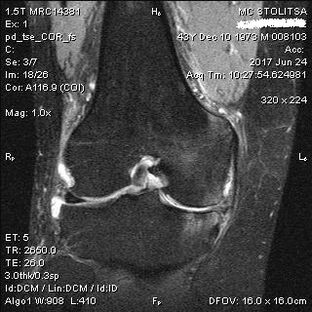

Artrose van het kniegewricht op MRI